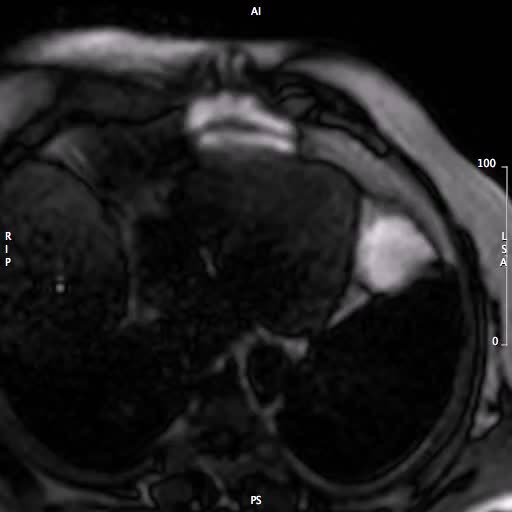

Le indicazioni e le controindicazioni alla RM cardiaca. Quando le informazioni fornite dalla TC sono fondamentali e quando superflue.

Cardiomiopatia ipertroficaAutore: Arturo Raisaro

Categoria: Videoalbum

Parole chiave: cardiomiopatia ipertrofica diagnosi rm -